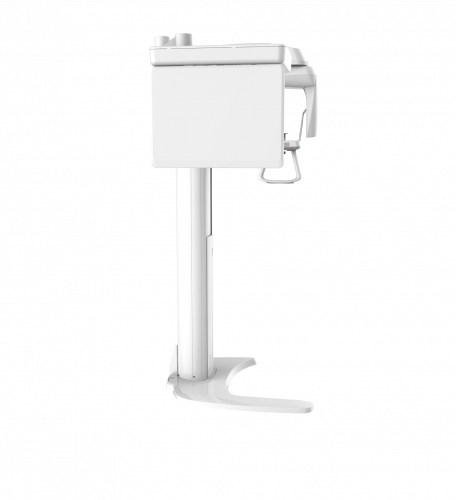

| TYPE | TOP VIEW | FRONT VIEW |

|---|---|---|

|

PaX-i (Pano) |

|

|

|

PaX-i SC (Pano/Scan Ceph) |

|

|